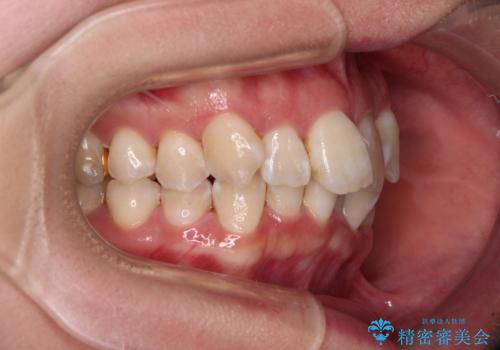

- 前歯1本が後ろ側に隠れてしまうほどのデコボコを気にして来院された患者様です。

前歯のデコボコが顕著なのはもちろんですが、左右ともに奥歯の咬み合わせに問題があり、上顎臼歯が前方位にある状態でした。

上顎は左右の第一小臼歯2本を、下顎は左右第二小臼歯2本を抜歯することで、奥歯の咬み合わせを改善しながら、デコボコを解消していくこととしました。

奥歯の咬み合わせ改善にはどうしても長期間を要します。

3年強とお伝えしておりましたが、予想通り3年3ヶ月で治療を終えることができました。